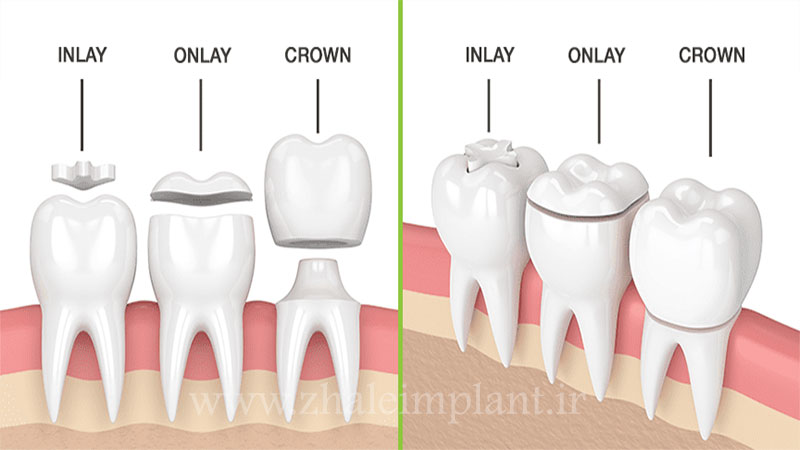

اینله دندان چیست؟

این روش مانند پر کردن دندان است، ولی زمانی از آن استفاده میشود که حفره و پوسیدگی ایجاد شده در دندان عمیق باشد. اینله برای ترمیم قسمتهای سطوح جوند و شیارهای دندان کاربرد دارد.

انله دندان چیست؟

آنله هم مانند اینله روشی برای ترمیم دندان است با این تفاوت که از انله در پوسیدگیهای عمیقتر و گستردهتری که لبه ها نیز درگیر هستند استفاده میشود، رنگ آن مانند اینله همرنگ با رنگ طبیعی دندان است.

دندان دارای 4 لبه است، برای پوسیدگیهای عمیق که همه لبههای دندان درگیر باشند انله کاربرد دارد و همه لبههای سطح دندان را پوشش میدهد.

زمانی که پوسیدگی دندان به حدی بالا باشد که با پر کردن معمولی یا اینله و انله قابل درمان نباشد اخرین راه نجات روکش دندان است. در این روش، روکش جایگزین کل قسمت بیرونی دندان یعنی تاج میشود ولی ریشه دندان سالم است، ولی در اینله و انله فقط سطح بالای دندان و قسمت داخلی یعنی لبه و شیارها ترمیم میشوند.